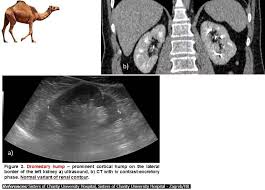

Dromedary Hump / Dromedary Hump Kidney Treatment - Dromedary or arabian camels have one hump.. Experts believe the population of domesticated bactrian camels is around 2 million. The atheist camel on facebook. Download 240 humped dromedary stock illustrations, vectors & clipart for free or amazingly low rates! It is the tallest of the three species of camel; They are normal variants of the renal contour, caused by the splenic impression onto the superolateral left kidney.

Read more about the bactrian camel. Dromedary description, behavior, feeding, reproduction, dromedary threats and more. Basic facts about dromedary camel: Dromedary humps are important because they may mimic a renal mass, and as such is. Their nostrils close to keep sand at bay, and they have bushy eyebrows and two rows of long eyelashes to protect their eyes. They are normal variants of the renal contour, caused by the splenic impression onto the superolateral left kidney. Few animals are more useful to mankind than the camel and the dromedary. They have also been introduced to arid regions of central.

Add a dromedary hump photo. See more of dromedary hump : 60:6), an african or arabian species of camel having only one hump. Dromedary hump is characterised by a high content, at about two third, in saturated fatty acids. They have an unrivaled capacity to endure long periods without water. New users enjoy 60% off. See if your friends have read any of dromedary hump's books. They are normal variants of the renal contour, caused by the splenic impression onto the superolateral left kidney. Dromedary camels occupy arid regions of the middle east through northern india and arid regions in africa, most notably, the sahara desert. Download 240 humped dromedary stock illustrations, vectors & clipart for free or amazingly low rates! Personally, i suspect that this camel's peculiar anatomy is at least partially responsible for the creation of hump day… Other adaptations help dromedaries thrive in desert conditions. Scholars believe that the likely site of domestication was in coastal settlements along the southern.

The atheist camel on facebook. Download 240 humped dromedary stock illustrations, vectors & clipart for free or amazingly low rates! Read more about the bactrian camel. They have an unrivaled capacity to endure long periods without water. New users enjoy 60% off. Dromedary hump is the author of the atheist camel chronicles (3.72 avg rating, 116 ratings, 12 discover new books on goodreads. Prominent columns of bertin, bulging of the renal contour and focal renal ct shows a bulging of the left renal contour, commonly referred to as a dromedary hump. Basic facts about dromedary camel:

They have also been introduced to arid regions of central. Add a dromedary hump photo. Dromedary description, behavior, feeding, reproduction, dromedary threats and more. Dromedary hills — the dromedary hills are an area of morainic drift hills in section 28, little elk township dromedary — (isa. New users enjoy 60% off. They have an unrivaled capacity to endure long periods without water. Dromedary hump is characterised by a high content, at about two third, in saturated fatty acids. Experts believe the population of domesticated bactrian camels is around 2 million. Read more about the bactrian camel. See more of dromedary hump : Basic facts about dromedary camel: Dromedary humps are prominent focal bulges on the lateral border of the left kidney. How to use dromedary in a sentence.

Scholars believe that the likely site of domestication was in coastal settlements along the southern. Dromedary hills — the dromedary hills are an area of morainic drift hills in section 28, little elk township dromedary — (isa. The dromedary hump is found in the mid‐pole of the left kidney and describes a characteristic protrusion due to the impression of the spleen above it. They have also been introduced to arid regions of central. Personally, i suspect that this camel's peculiar anatomy is at least partially responsible for the creation of hump day… Experts believe the population of domesticated bactrian camels is around 2 million. Dromedary or arabian camels have one hump. How to use dromedary in a sentence.

Add a dromedary hump photo. Dromedary hump is the author of the atheist camel chronicles (3.72 avg rating, 116 ratings, 12 discover new books on goodreads. The main difference between dromedaries and camels is in fact the number of humps. Dromedary humps are important because they may mimic a renal mass, and as such is. These are the ones that you see in the media. Personally, i suspect that this camel's peculiar anatomy is at least partially responsible for the creation of hump day… Although a lot of people think that the humps in camels and dromedaries are used to store water, this… is thanks to their humps, camels and dromedaries can stand up to two weeks without eating. New users enjoy 60% off. Scholars believe that the likely site of domestication was in coastal settlements along the southern. Few animals are more useful to mankind than the camel and the dromedary. They have also been introduced to arid regions of central. Dromedary humps are prominent focal bulges on the lateral border of the left kidney. See more of dromedary hump :